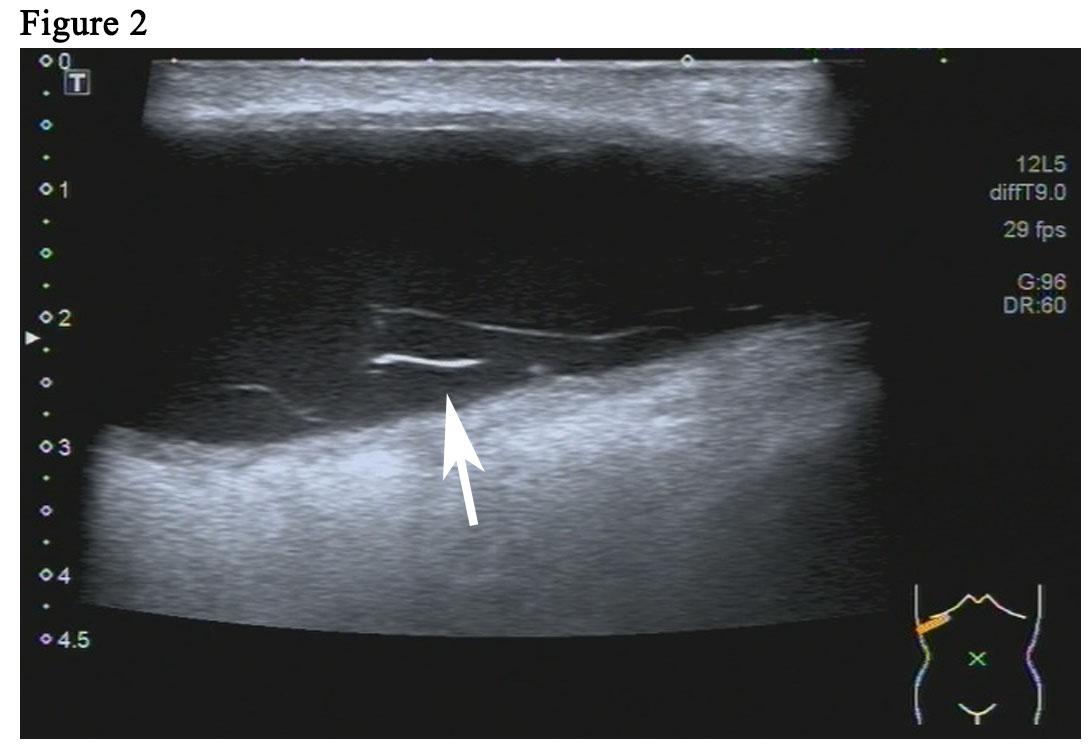

The patient is a 59-year woman. She had a mass for one month in the left upper outer quadrant region of the right breast. The patient had no past medical history or family history of breast cancer. Physical examination showed a mass of 3cm × 3cm sized, which was mildly tender and firm. The surface skin of mass was not ruptured. Lymph nodes of axillary and supraclavicular were not palpable. Ultrasound examination (Figure 1A) revealed a welldefined hypoechoic mass without calcification or evidence of invasion, which was 3.0cm × 2.6cm in size for the breast. The markers of erum tumor and other routine blood tests were normal. The bdominal and axillary lymph node ultrasound, chest X-ray and bone scan were normal. The patient was performed an excisional biopsy as an outpatient. Histopathology of a fast frozen section results showed an invasive ductal carcinoma. Following the diagnosis, she underwent a modified radical operation. The pathologist also confirmed there was an invasive ductal carcinoma (Figure 1B). 7 of the 22 dissected axillary lymph nodes demonstrated evidence of disease and the surgical margins were negative. The estrogen receptor (ER) was positive at 100%, progesterone receptor (PR) and human epidermal growth factor receptor-2 (Her-2) was negative. The tumor was pathologically staged as pT2N2M0 according with the eighth edition of the AJCC cancer [8]. An ultrasound of the patient’s breast was performed before she undertook the first cycle of chemotherapy. This ultrasound revealed a seroma of right chest wall measuring 7cm × 2.4cm in size (Figure 2). Then, the patient was performed adjuvant chemotherapy (AC) (doxorubicin + cyclophosphamide for 4 cycles, following by docetaxel cycled for 4 cycles). The patient then had another ultrasound of her breast after she had finished the last cycle of chemotherapy. The results of this ultrasound showed that the seroma of right chest wall now measured 10.8cm × 3.1 cm in size (Figure 3A). CT (computed tomography) scan also suggested a large seroma of the chest wall (Figure 3B). The seroma of the chest wall was enlarged compared with its size before starting chemotherpy. Once the round of chemotherapy was complete the patient then received adjuvant radiation therapy. The patient was treated with intensity modulate radiation therapy (IMRT). The planned dose was 50Gy (2.0 Gy/fraction x 25 fractions) to the affected areas (chest wall and regional lymph node). However, the patient had to stop radiotherapy when the accumulated dose was 38Gy, because she developed a soft tissue infection of chest wall. The right chest wall of secroma became red, swollen and painful. The region of infection was the same area where the seroma was (Figure 4A). Abscess had formed under the chest wall. Ultrasound revealed dense fine-dotted echoes in seroma (Figure 4B). The patient experienced a recurrent fever which resulted in her highest temperature being 39.8 ℃. A routine blood test revealed that leukocytes (14.9*10E9/L) and neutrophils (12.4*10E9/L) had increased significantly. C reactive protein (56.11mg/L) showed similar increases. The patient was then admitted to the Skin Repair Department. She was diagnosed with the right chest wall of secroma infection and abscess formation. The patient’s abscess was cut and discharged. Pathogen culture and drug sensitive test had was perform. Pseudomonas aeruginosa found in pus culture. Piperacillin sodium sulbactam, sodium cefmetazole sodium and ofloxacin were high sensitivity in drug sensitive test. She was then given antibiotics. The patient underwent three rounds of painful debridement and negative pressure treatment. Finally debridement and flap plasty was performed on the patient who then remained hospitalized for 2 weeks and after which went home for recuperation. Following discharge, the patient no longer had seroma and recovered well. She remains free of locoregional recurrence or distant metastases after 37 months of postoperative follow-up.

Figure 2: Ultrasound revealed a seroma (white arrow) of right chest wall Measuring 7.0cm× 2.4cm.